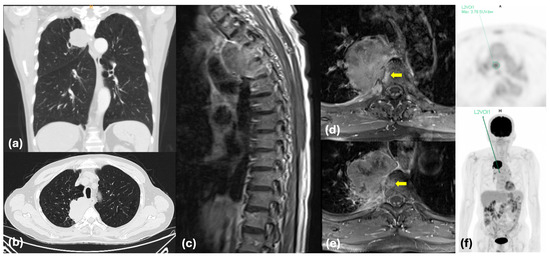

Oligoprogression in NSCLC with Other Actionable Oncogenic Drivers Beyond EGFR and ALK: An Emerging Entity

Oligoprogressive disease (OPD) in non-small-cell lung cancer (NSCLC) is a clinical entity with peculiar behavior and treatment. OPD patients, during systemic therapy, may receive local ablative treatment (LAT) with survival benefit. The importance of OPD and the role of LAT has been comprehensively [...] Read more.

Oligoprogressive disease (OPD) in non-small-cell lung cancer (NSCLC) is a clinical entity with peculiar behavior and treatment. OPD patients, during systemic therapy, may receive local ablative treatment (LAT) with survival benefit. The importance of OPD and the role of LAT has been comprehensively assessed in the setting of EGFR mutant and ALK-rearranged NSCLC during tyrosine kinase inhibitor (TKI) treatment, but it is still almost unexplored in the context of NSCLC harboring actionable oncogenic drivers other than EGFR and ALK. The aim of our review is to collect and discuss the available data about standard treatment in this latter setting, with special consideration given to the role of LAT in case of OPD in systemic treatment. Through a comprehensive PubMed and ClinicalTrials.gov search, we identified the available data and ongoing clinical trials addressing these aims. To date, only limited evidence supports the use of LAT in OPD involving NSCLC driven by these molecular alterations, mainly deriving from case reports and retrospective series. This highlights an unmet clinical need that warrants systematic and multicentric data collection to generate more robust evidence. Full article

Show Figures